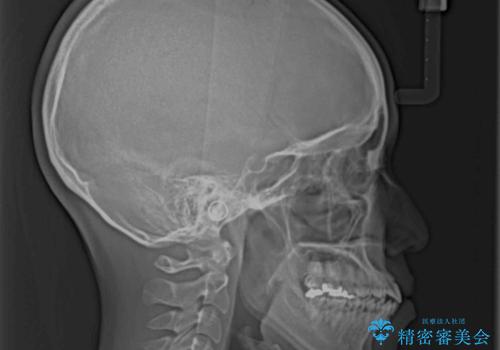

デコボコと口元の突出感が認められたため、上下左右の第1小臼歯4本を抜歯してのワイヤー矯正を行うこととしました。

上顎歯列の横幅が狭く、下顎大臼歯の歯軸が舌側に倒れていたため、急速拡大装置により上顎骨を側方に拡大し、咬み合わせを改善することとしました。